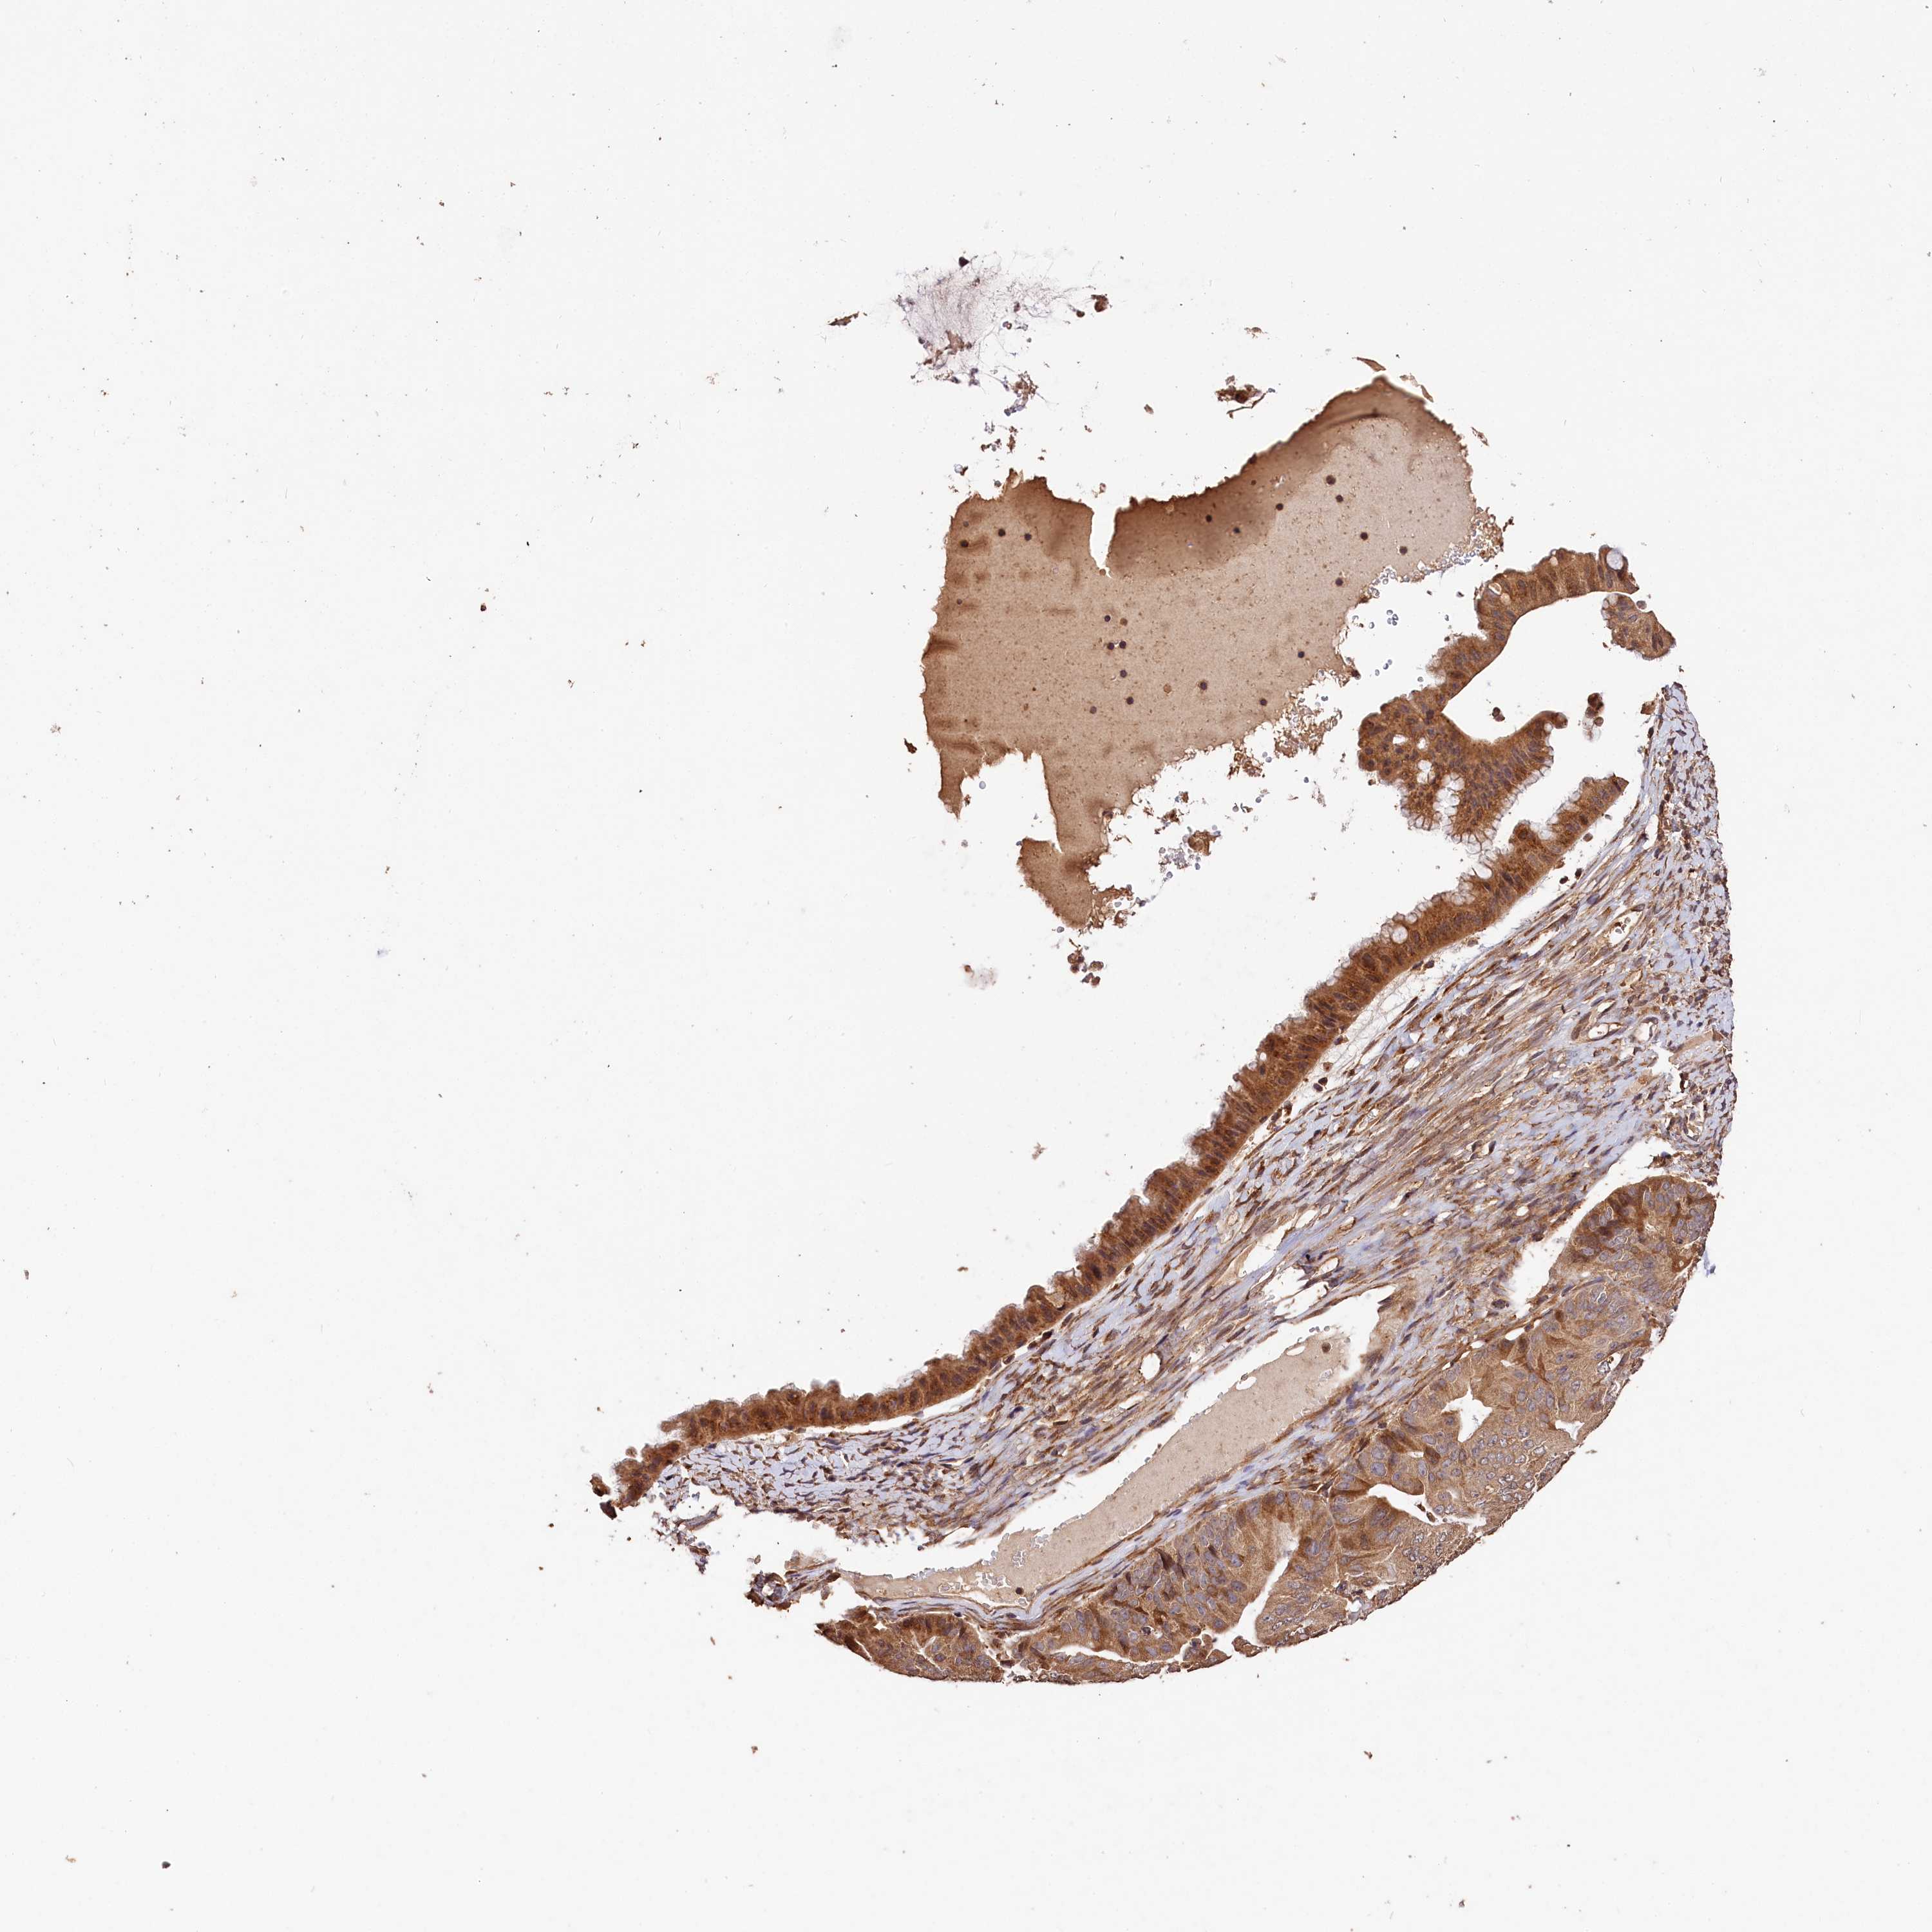

OVARIAN CANCER - Protein expressioni

A mouse-over function shows sample information and annotation data. Click on an image to view it in a full screen mode. Samples can be filtered based on level of antibody staining by selecting one or several of the following categories: high, medium, low and not detected. The assay and annotation is described here.

Note that samples used for immunohistochemistry by the Human Protein Atlas do not correspond to samples in the TCGA dataset.

Antibody stainingi

Antibody staining in the annotated cell types in the current human tissue is reported as not detected, low, medium, or high, based on conventional immunohistochemistry profiling in selected tissues. This score is based on the combination of the staining intensity and fraction of stained cells.

Each image is clickable and will lead to virtual microscopy that enables deeper exploration of all samples and also displays staining intensity scores, fraction scores and subcellular localization as well as patient and tissue information for each sample.

Antibody HPA041710

Antibody HPA041796

Staining

High

Medium

Low

Not detected

Intensity

Strong

Moderate

Weak

Negative

Quantity

>75%

75%-25%

<25%

None

Location

Nuclear

Cytoplasmic/membranous

Cytoplasmic/membranous,nuclear

Cystadenocarcinoma, serous, NOS

Carcinoma, endometroid

Cystadenocarcinoma, mucinous, NOS

Carcinoma, NOS